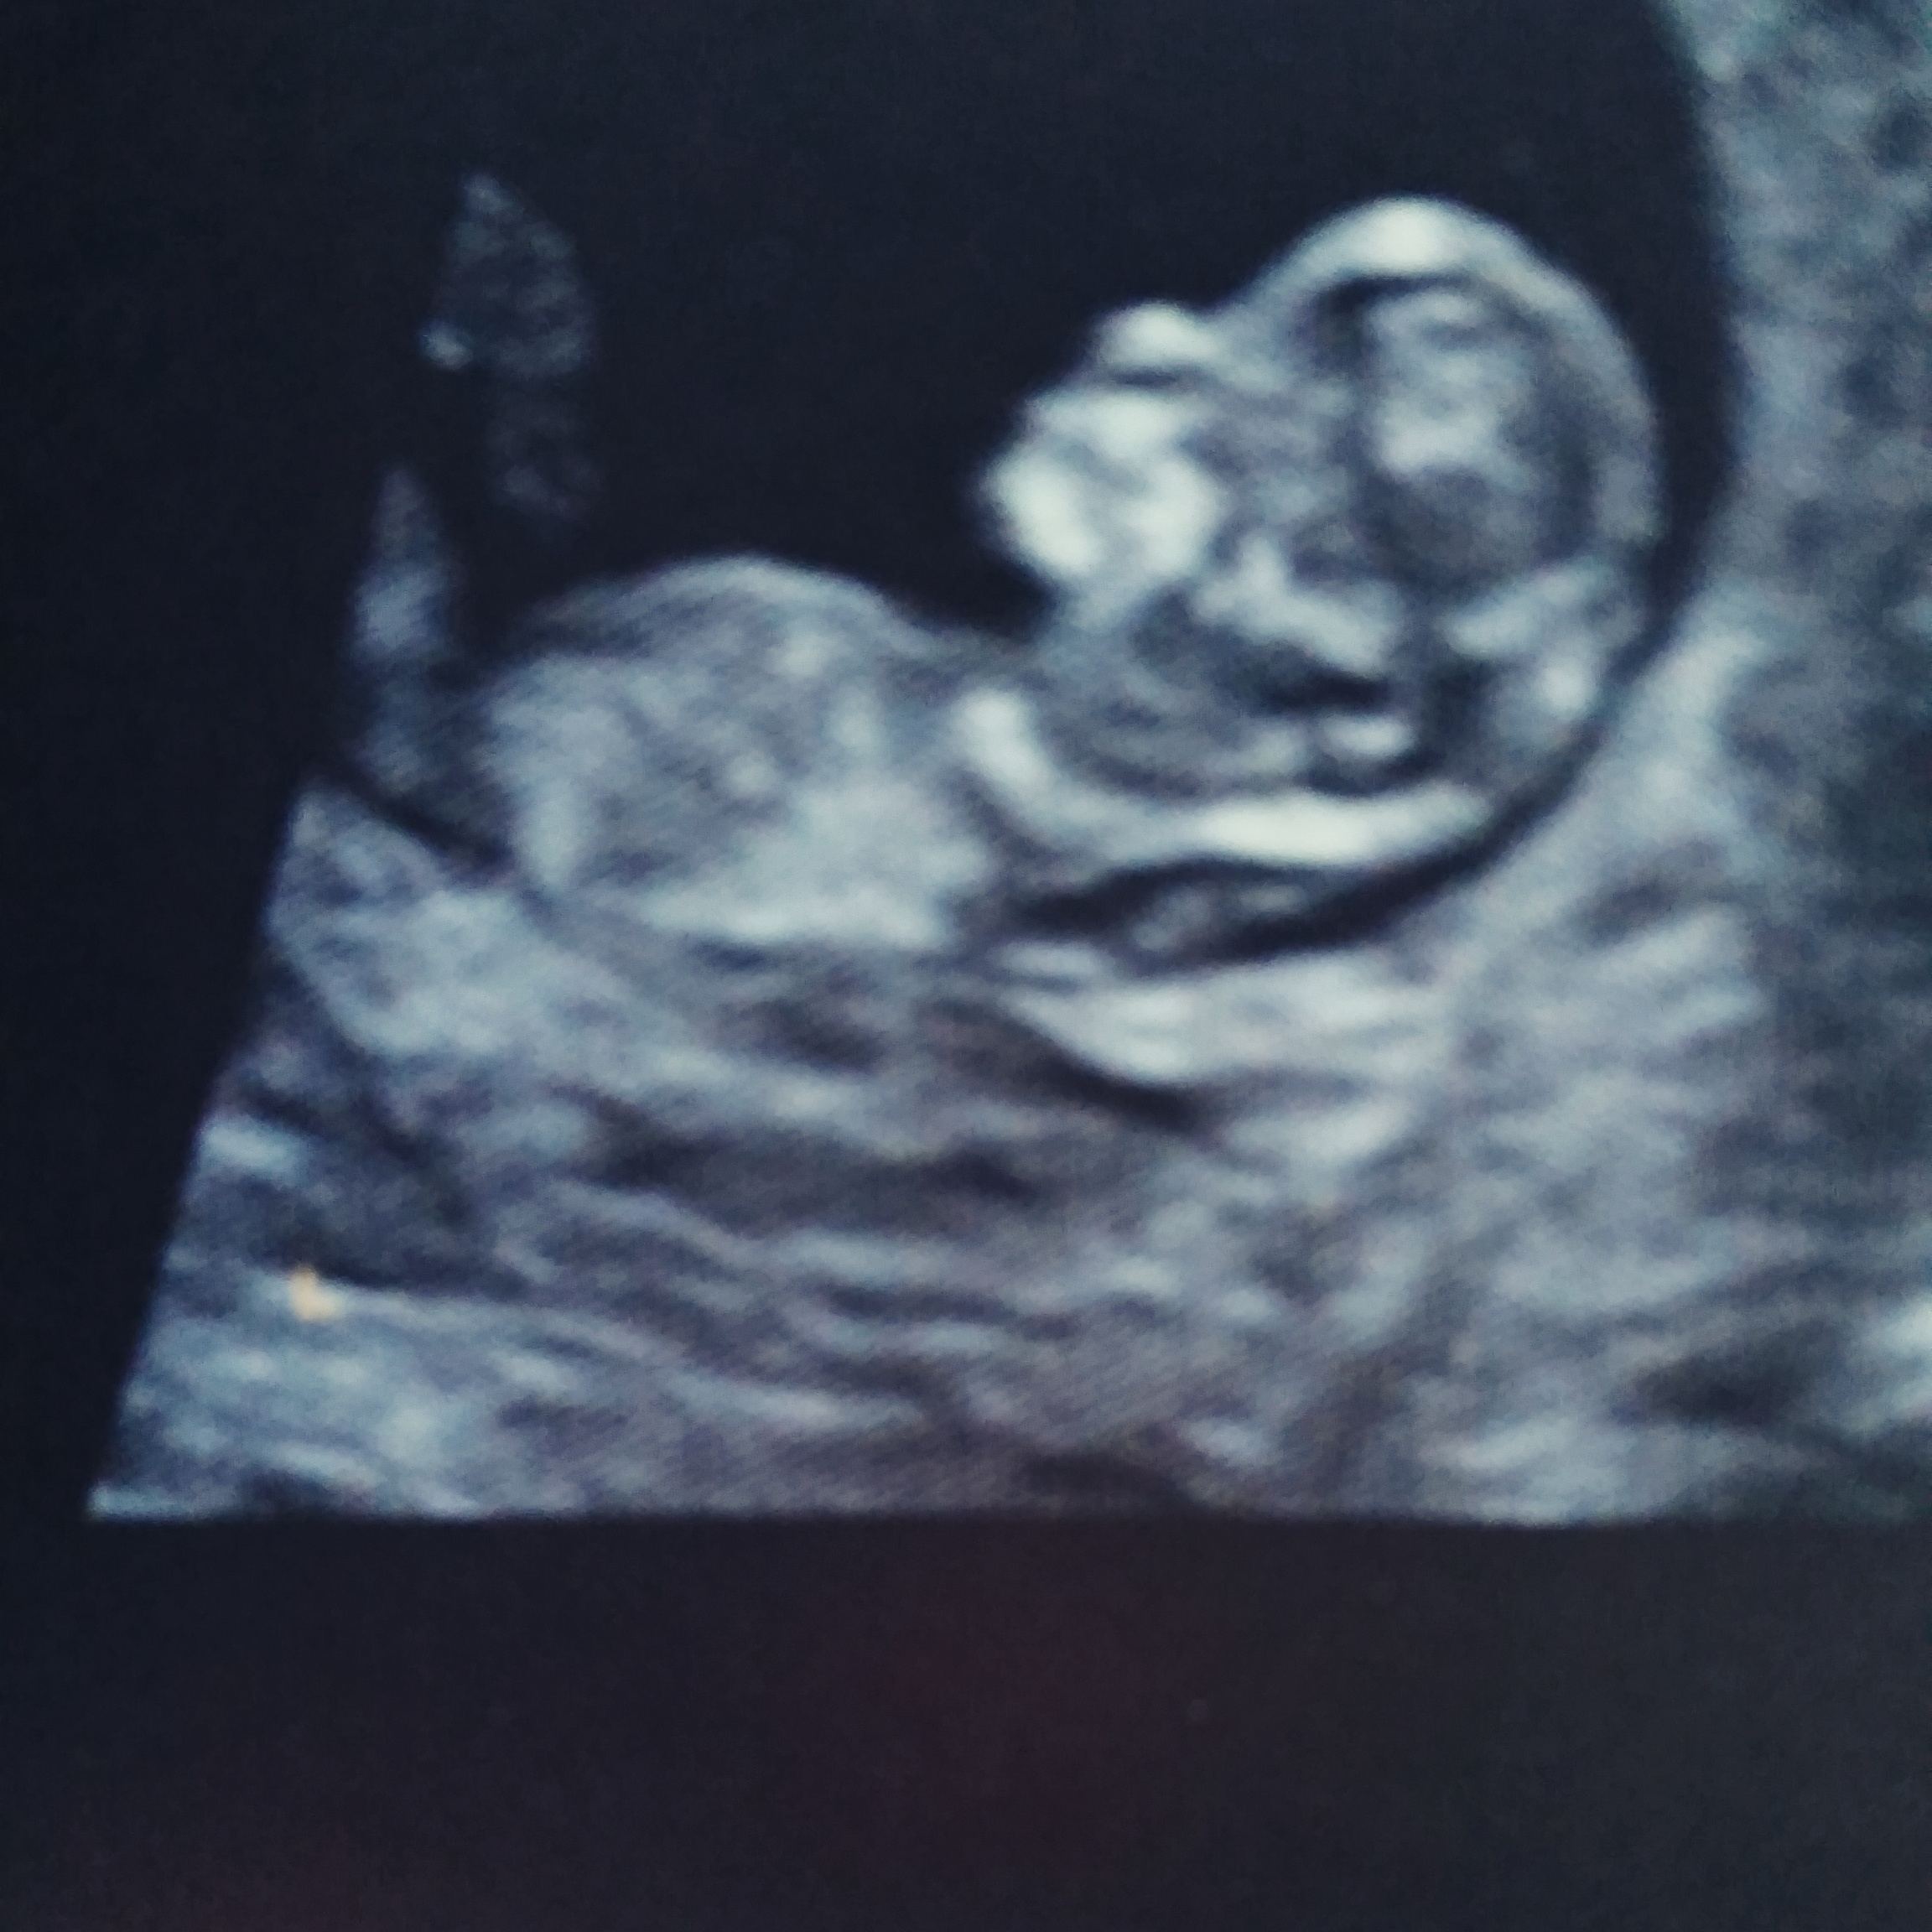

can you please tell me if baby is pink or blue.

The photo is directly between legs at 11.5 weeks along.

I think most people will tell you 11.5 is a bit too early to make any confident guess as most will look more girl as this does.